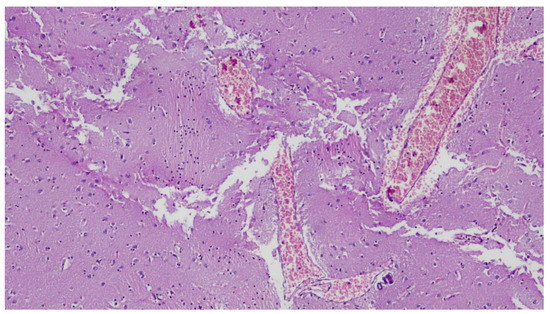

2. Case Presentation